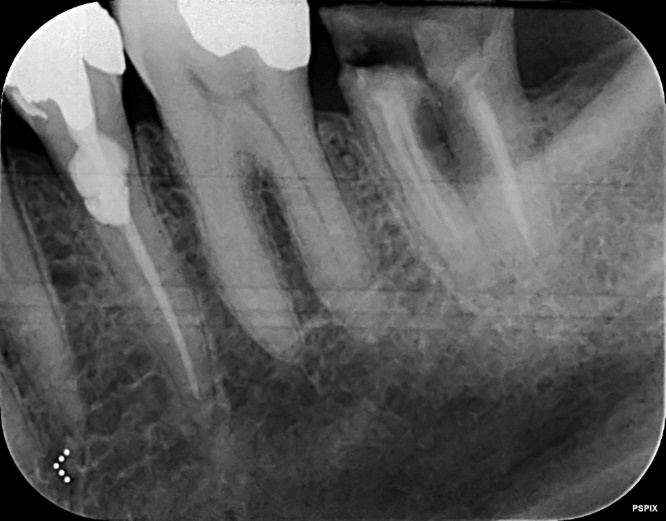

Lower Re-root canal treatment through dental crown